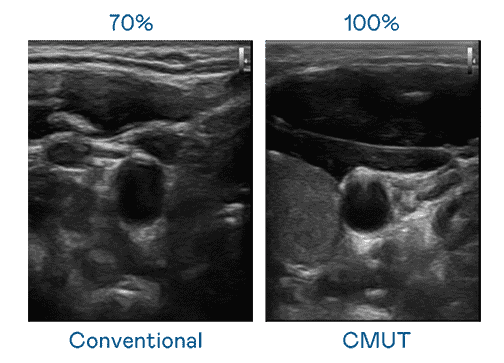

CMUT 技术是一种用电容式微机电元件来产生超音波讯号的技术。。。与传统 PZT 压电式技术相比,,,,CMUT 频宽增加 30%,,更宽频的超音波讯号让影像解析度大幅提升,,是实现高影像品质医疗超音波扫描、、、、促进精准医疗发展的关键技术。。。

超音波影像的解析度高低,,,,首先取决于探头能发出的讯号频宽。。。至成国际 CMUT 可提供高清晰的超音波讯号,,提供高频宽、、、、高灵敏度、、、、影像纹理细节更高的超音波影像,,协助医护人员缩短影像判读时间及利用精准的医疗影像进行诊断。。。。